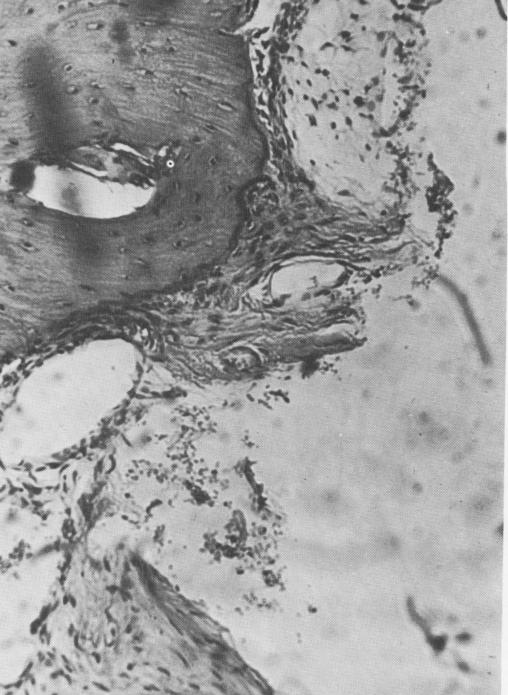

All the metallic implants were separated from the bone by a fibrous tissue membrane (Fig. 4-67). The bone was dense, with numerous osteocytes, and there was no sign of inflammation of either the fibrous tissue membrane or the bone (Fig. 4-68). Near the base of the implant the formation of blood vessels was evident (Fig. 4-69). Also, the fatty mar-row tissue looked normal. In another view of the base of the implant the organization of the connective tissue and blood vessel formation are clear (Fig. 4-70) .

Fig. 4-68. Under higher magnification, osteocytes can be seen in the bone and osteoblastic activity around the periphery. Note the absence of inflammatory activity. (Courtesy K. R. Blakey, Howard University.)

1 Bone tissue around implant with osteocytes and osteoblastic activity